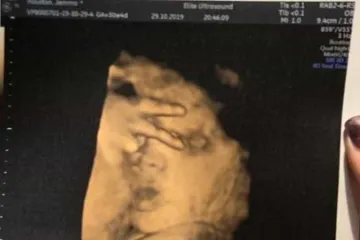

Ամերիկյան ֆուտբոլի մարզիչը նկատողություն է ստացել, երբ իր թիմը չափազանց մեծ հաշվով է հաղթել մրցակցին Գիտնականները սրտի հիվանդությունների եւ քաղցկեղի զարգացման վտանգի միջեւ կապ են գտել Թբիլիսիում փոքր տղային դանակով վիրավորած կնոջը հարկադիր բուժման են ուղարկել Նրանք ինտեգրվել են, բայց չեն ձուլվել. Բաշար Ալ–Ասադը խոսել է սիրիահայերի մասին Արմավիրի մարզի Շենավանի գյուղապետը ձերբակալվել է. նա կասկածվում է անձի առեւանգման մեջ Իշխանություն առանց էթիկական կոդեքսի․ Վահան Իշխանյան Ռուս ուղղափառ եկեղեցին խզում է կապերը Հունաստանի ուղղափառ եկեղեցու հետ Գեղեցկության միջազգային մրցույթում Հնդկաստանի ներկայացուցիչը դարձել է «Միսս Կոսմո աշխարհ» Ֆրանսիայում Պակիստանի քաղաքացիներով բեռնատար են բռնել Ինչո՞ւ են «Երևանի» հայ ֆուտբոլիստները բոյկոտել գավաթային հանդիպումը Արցախի բանակի հրամանատարը նոր կոչումներ է շնորհել զորավարժությանն աչքի ընկած սպաներին Սաուդյան Արաբիայի արքայազնը «կանաչ լույս» է վառել երկրի պատմության խոշորագույն գործարքի համար «Լեւանտեն» պարտության մատնեց «Բարսելոնային» (տեսանյութ) 3 տարի շարունակ հետախուզվողին գտել են Համբուրգում ու տեղափոխել Երեւան Զիդան. Ռեալն A ու B կազմ չունի, ես բոլորի վրա հույս եմ դնում Իլոն Մասկը գովել է Ալեքսիս Օհանյանի Reddit ցանցը Հոլիվուդյան աստղ Ջեյն Ֆոնդան մի ամբողջ գիշեր է անցկացրել բանտում կլիմայական ակտիվիստների ակցիային մասնակցելու պատճառով «Բավարիայի» անսպասելի պարտությունը՝ 1։5, «Բորուսիաների» հաղթանակները Քանի՞ անվանակրգում Joker-ն «Օսկարի» կառաջադրվի «Ռոման» հաղթեց «Նապոլիին» առանց Մխիթարյանի Աֆղանստանում 8 երեխա է զոհվել դպրոցի մոտակայքում ռումբի պայթյունի հետեւանքով Գազիֆիկացվել է Նուբարաշեն վարչական շրջանի Բ թաղամասը Մոսկվայում և Մերձմոսկվայում եղանակային վտանգի «դեղին» մակարդակ է հայտարարվել Հայաստանի գավաթ. «Սևանն» ու «Վանը» դուրս եկան քառորդ եզրափակիչ Մալազիան Եվրոպային սպառնացել է ռուսական ինքնաթիռներ գնել Ղրղզստանի նախագահը հայտարարել է, որ պաշտոնավարման ավարտից հետո այլևս չի առաջադրվի Սիրիայում պայթյուն է որոտացել թուրքական բանակի վերհսկողության տակ գտնվող քաղաքում. 10 մարդ մահացել է Հոնկոնգում ցուցարարները հարձակում են գործել չինական Xinhua տեղեկատվական գործակալության վրա Սենատում քննարկվելու է Հայոց ցեղասպանությունը ճանաչող մեկ այլ բանաձեւ ԱՄՆ-ում 18-ամյա աշակերտը փորձել է քիլեր վարձել դպրոցի աշխատակիցներից մեկին սպանելու համար Սարատովում հայրը բռնել է տղամարդուն, որը փորձել է առեւանգել իր 10-ամյա աղջկան «Ուզում են ժողովրդին ահաբեկել». բնապահպանը` Ամուլսարի ճանապարհների ապաշրջափակելու մասին Դավիթ Տոնոյանը ՌԱԿ պատվիրակությանը ներկայացրել է բանակում լայնածավալ բարեփոխումների ընթացքը Ո՞վքեր են հայոց ցեղասպանության H. Res. 296 բանաձևի դեմ քվեարկած ԱՄՆ Ներկայացուցիչների պալատի 11 կոնգրեսականները 62-ամյա կինը միկրոավտոբուսում փող ու զարդեր էր գողացել. ոստիկանության բացահայտումը Գագիկ Խաչատրյանին մեղսագրվող արարքների հետևանքով ավելի քան 7 մլրդ 3 միլիոն դրամի վնաս է հասցվել. ԱԱԾ «Դուխով» նստարաննե՞րն էլ է Սերժ Սարգսյանինը եղել Արարատ Միրզոյանն ընտրվել է ԱԺ նախագահ՝ լինելով ՀՀ առաջին փոխվարչապետի պաշտոնակատար Քոչարյանի ազատման համար հարթակ է ստեղծվել Դեռ չծնված երեխան ուլտրաձայնային հետազոտության ժամանակ հաղթանակի՝ «V» նշանն է ցույց տվել՝ ապշեցնելով բժիշկներին Ո՞նց կարար Գեւորգ Կոստանյանը ինձ գար ասեր` այս թուղթը փոխի Լարվածությունը համեմատաբար ակտիվ էր. Դավիթ Բաբայանը՝ սահմանային իրավիճակի մասին Ֆրանսիային է մոտենում «Ամելի» փոթորիկը Մարտաֆիլմ հիշեցնող սպանություն Նորատուսում. 20-ից ավելի կրակոցից կա 1 զոհ, 1 վիրավոր.վարկածներից մեկը վենդետան է Վերջին տուրում Հայաստանի հավաքականը հաղթանակ տարավ Սուրճը, գազավորված ըմպելիքները, արմավենու յուղը. ո՞ր մթերքներն են կալցիումը դուրս բերում օրգանիզմից Անպատասխանատու քայլ է «Ռազմագիտությունը» դպրոցական ծրագրից հանելը․ ռազմական փորձագետ Հանրապետության թիվ 1 առանձնատան մասին. Նիկոլ Փաշինյանը ուղիղ եթերում է Գագիկ Հարությունյանը շարունակո՞ւմ է լինել ՍԴ նախագահ․ փաստաբան (տեսանյութ) Ռոնալդուի մայր. Ֆուտբոլային մաֆիան չի թողնում, որպեսզի Կրիշտիանուն «Ոսկե գնդակ» նվաճի